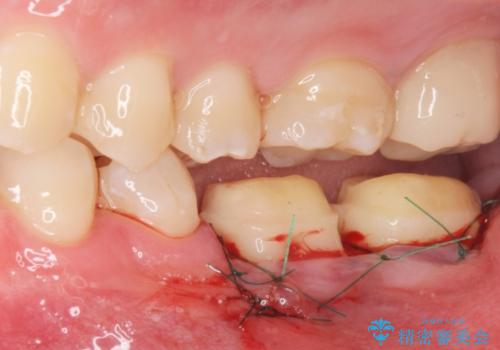

APF(歯肉弁根尖側移動術)

銀歯を外して被せ物の予定でしたが歯の高さが低く取れやすい被せ物になってしまうため歯の高さを変える手術を行いました。

治療後の写真は2週間後の写真です。歯茎の治癒が完全に治るのは半年くらいかかるので半年後に最終的な被せ物を入れる予定です。